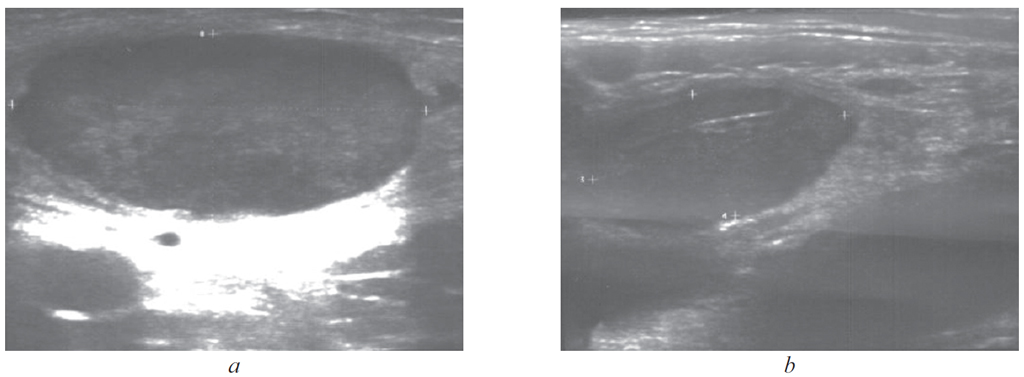

На 24-й день заболевания (07.09.2020) повторно осмотрен инфекционистом детской поликлиники: сохранялись субфебрильная температура, увеличение лимфоузлов паховой области слева до 3,5 см, справа — до 2,0 см. При пальпации лимфоузлы чувствительные слева, подвижные, не спаяны между собой и окружающими тканями, кожа над ними не изменена. Остальные группы лимфоузлов не увеличены. Со стороны ЛОР-органов и органов грудной клетки патологических изменений не отмечено. Гепатомегалия до +1,5 см, селезенка не пальпировалась. Стул, диурез без особенностей. Менингеальные и очаговые симптомы отрицательные. По результатам лабораторного обследования от 02.09.2020 (19-й день болезни): в клиническом анализе крови — ускорение СОЭ до 44 мм/ч (табл. 1), УЗИ органов брюшной полости — незначительная гепатомегалия без изменения эхоструктуры паренхимы, УЗИ паховых лимфоузлов: увеличение слева до 3,9 × 1,5 × 3,0 см, края четкие, неровные, структура паренхимы неоднородная с гипер- и гипоэхогенными включениями, окружающие ткани не изменены (см. рисунок, a), справа — до 2,1 × 1,0 см, структура паренхимы и окружающих тканей не изменены (b). При серологическом исследовании от 02.09.2020 обнаружены высокие титры противотуляремийных антител: в реакция агглютинации — 1 : 800 (диагностический титр 1 : 400 и выше) [6], в реакции пассивной гемагглютинации — 1 : 10240 (табл. 2). На основании клинико-эпидемиологических и лабораторных данных диагностирована туляремия (гландулярная форма, легкая степень тяжести). Для дальнейшего лечения и обследования ребенок с приема госпитализирован в инфекционное отделение детской городской больницы.

Рисунок. Ультразвуковое исследование паховых лимфоузлов ребенка, 13 лет, больного туляремией: а — увеличенный лимфоузел слева с четкими краями, неоднородной структурой паренхимы с гипер- и гипоэхогенными включениями; b — справа, не увеличен, структура паренхимы и окружающих тканей не изменены / Figure. Results of ultrasound examination of the inguinal lymph nodes of a 13-year-old child with tularemia: а – enlarged lymph node with clear edges, heterogeneous structure of the parenchyma with hyper- and hypoechoic inclusions; b – not increased, the structure of the parenchyma and surrounding tissues is not changed